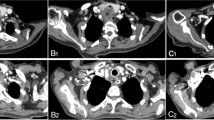

Efficacy and bio-toxicity of the LZ61-KBMS tracheal stents were tested in normal New Zealand rabbit trachea model chosen based on literature report43. The LZ61-KBMS or 316L SS stent (Fig. 3A) was placed beneath the first airway cartilage ring confirmed by X-ray imaging of the rabbit neck (Fig. 3B). LZ61-KBMS is hardly visible under the X-ray due to the lower density of the LZ61-KBMS alloy (Fig. 3B (ii)). Endoscopic (Fig. 3C) and optical coherence tomography (OCT) imaging (Fig. 3D) were performed at the end of each time point with endoscopic imaging of LZ61-KBMS at week 4 for monitoring stent structure and position.

A The surgical procedure of the stent placement. (i) Tracheal stent was mounted on the balloon. (ii) The balloon was injected with saline and expanded the tracheal stent against the tracheal wall. (iii) The balloon was deflated and pulled out of the trachea leaving the stent inside the tracheal lumen. B X-ray image of the implantation site of the (i) 316L SS stent and (ii) LZ61-KBMS stent after the tracheal stent implantation. The positions of the stents are circled in the images. LZ61-KBMS stent is hard to identify here under the X-ray due to the lower density. A dark shadow is only visible here. C Endoscopic images of the stented airway right after implantation, and after 4, 8, and 12 weeks of implantation. D OCT images of the cross-section of the stented airway at 4, 8, and 12 weeks after implantation. E Tracheal lumen area calculated based on the cross-section of OCT images at 4, 8, and 12 weeks. **denotes a significant difference between alloy groups (p < 0.01, n = 3). F The 3D structure of 316L SS stents and LZ61-KBMS stents based on µCT scan at different time point indicating the remaining stents after implantation in vivo.

The OCT images indicated LZ61-KBMS stent encapsulation in the airway tissues with visible gas pockets due to H2 gas release during stent degradation contributing to the airway tissues porosity surrounding the stents. The gas pocket formation is common for magnesium alloy-based implants44,45,46, but their effect on airway tissue is unknown to date. The airway stented with 316L SS stent appeared similar to LZ61-KBMS under the endoscope except as expected, there was no gas pocket around the 316L SS stent validated by the OCT images. At 8 weeks, for the LZ61-KBMS, there was no visible stenotic tissue formation, and the trachea lumen appeared healthy. OCT scanning also further verified complete stent degradation with airway lumen restoration to its normal smooth surface. In contrast, endoscopy imaging indicated steady stenotic tissue growth in the 316L SS stent group at both weeks 8 and 12 in line with the 8 and 12 weeks OCT results. Stenotic tissue growth is typical for non-degradable metallic stents47. It is hence, critical to understand the stent’s implantation impact on tracheal lumen size in growing rabbits, since this is a key indicator of normal pediatric patient respiratory function after receipt of tracheal stent implants over the stent degradation period and its effect and interference on overall natural tracheal growth. Therefore, we calculated the tracheal lumen size with the stents implanted inside based on the OCT images using the Image J software (Fig. 3E).

The lumen size of the LZ61-KBMS implanted trachea increased steadily with time as the rabbits continued to grow confirming no adverse impact on the growth upon LZ61-KBMS implantation and degradation. In contrast, with the 316L SS stents, the airway lumen size decreased with continued whole airway growth (Fig. 3E). The airway lumen size of the 316L SS control was significantly smaller than the LZ61-KBMS group at weeks 8 and 12 (p < 0.01) due to granulation tissue growth observed by endoscopy and OCT imaging of the non-degradable control group. The 3D structures of the remaining stents reconstructed based on the µCT scan (Fig. 3F) shows expectedly stable 316L SS stent structure preservation over the entire implant duration. However, for the LZ61-KBMS group, 53 ± 12% of the initial volume degraded after 4 weeks, fully degrading at week 8 supporting the endoscopy and OCT imaging results.